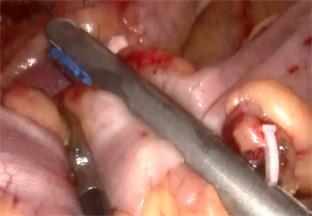

• 不同入路脊柱内镜手术治疗L4/5节段脱垂型腰椎间盘突出症的疗效比较

摘要:目的 观察经椎间孔入路内镜下腰椎间盘切除术(TELD)和经椎板间入路内镜下腰椎间盘摘除术(IELD)治疗L4/5节段脱垂型腰椎间盘突出症(LDH)的临床疗效。方法 回顾性分析2020年11月-2022年11月该院采用脊柱内镜手术治疗的75例L4/5节段脱垂型LDH患者的临床资料。根据手术入路的不同,将患者分为TELD组(53例)和IELD组(22例)。比较两组患者的手术情况和术后疗效。结果 与TELD组比较,IELD组的手术时间明显缩短,术中透视次数明显减少,差异均有统计学意义(P < 0.05);两组患者住院时间和并发症发生率比较,差异均无统计学意义(P > 0.05)。所有患者术后均获得12~19个月的随访。两组患者末次随访时的视觉模拟评分法(VAS)评分和Oswestry功能障碍指数(ODI)明显低于术前,且IELD组明显低于TELD组,差异均有统计学意义(P < 0.05)。按照突出物和神经根的不同位置进一步分析,两组肩上型患者(TELD组10例,IELD组6例)末次随访时的VAS评分和ODI明显低于术前,且IELD组末次随访时的VAS评分明显低于TELD组,差异均有统计学意义(P < 0.05);两组腋下型患者(TELD组8例,IELD组16例)末次随访时的VAS评分和ODI明显低于术前,且IELD组明显低于TELD组,差异均有统计学意义(P < 0.05);35例肩前型患者经TELD术后,末次随访时的VAS评分和ODI明显低于术前,差异有统计学意义(P < 0.05)。按照突出物的不同Lee分区进一步分析,两组Lee Ⅲ区患者(TELD组44例,IELD组10例)末次随访时的VAS评分和ODI明显低于术前,且IELD组的ODI明显低于TELD组,差异均有统计学意义(P < 0.05);两组Lee Ⅳ区患者(TELD组9例,IELD组12例)末次随访时的VAS评分和ODI明显低于术前,且IELD组明显低于TELD组,差异均有统计学意义(P < 0.05)。结论 采用TELD和IELD治疗L4/5节段脱垂型LDH,均可获得较满意的减压效果,但IELD的手术时间相对较短,X线透视次数较少,且对肩上型、腋下型、Lee Ⅲ区和Lee Ⅳ区的减压效果更有优势。